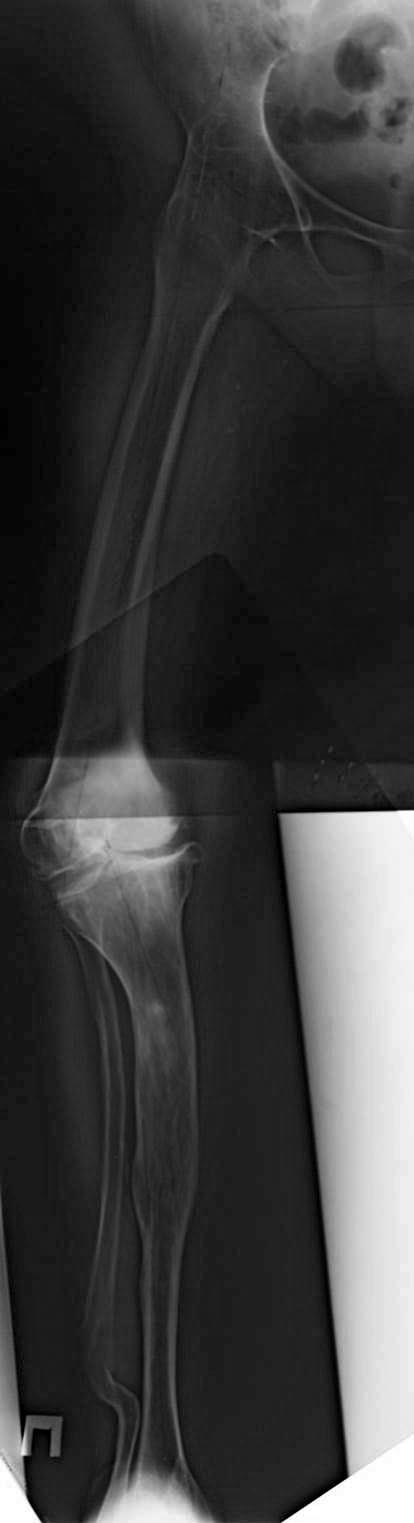

Обратилась дама около 60 лет, выскокоинтеллектуальная, с жалдобами на

боль в левом тазобедренном ввиду обычного артроза. Год с лишком назад

было выполнено успешное эндопротезирование левого тазобедренного

сустава. ZCA-CPT. Стоит хорошо. Чашка с антеверсией 20, наклон - 50.

Уверовав в силу эндопротезирования, обратилась с жалобами на

боль в правом колене. Рентген во вложении. Анамнез - в детском возрасте

- неуточненная операция по поводу "туберкулеза" на голени (рубец по

передней поверхности в верхней трети 15 см) и на тазобедренном суставе

(рубца не видно).

Статус - сгибание в к/с 100 градусов. Разгибание - полное. Колено

стабильно. Хочет эндопротез колена.